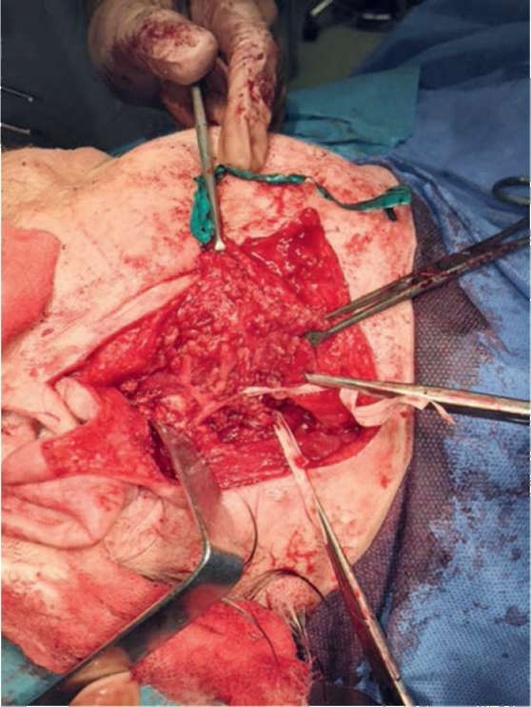

Разрез кожи начинается в предушной области вдоль основания козелка ушной раковины и, окаймляя мочку уха, проходит в заушную область, откуда направляется вдоль переднего края кивательной мышцы (рис. 6.19-6.22).

Далее отмобилизовывается кожно-жировой лоскут, рассекается поверхностная фасция. Идентифицируется передний край кивательной мышцы, который отмобилизовывается, далее препаровка продолжается в области хрящевой части наружного слухового прохода, отделяя слюнную железу от него на всем протяжении.

Идентифицируем заднее прикрепление двубрюшной мышцы, которая находится прямо за шилососцевидным отверстием. Шиловидный отросток пальпируется, что определяет глубину диссекции.

Далее плоскость тупой диссекции направлена перпендикулярно заднему полюсу слюнной железы.

При крупных опухолях заднего полюса ОСЖ необходимо сначала его отмобилизовать, идентифицировать заднее брюшко двубрюшной мышцы (его прикрепление), отводя передний край кивательной мышцы назад. При идентификации прикрепления заднего брюшка двубрюшной мышцы мы идентифицируем сосцевидный отросток височной кости, который находится прямо за шилососцевидным отверстием, таким образом приводя хирурга к ЛН с нижней стороны (рис. 6.23).

После идентификации ствола ЛН поверхностная доля железы рассекается путем вскрытия пространства, в котором ветви ЛН проходят между двух долей.

В толще слюнной железы ствол ЛН разделяется на 2 части - большая часть, именуемая скулолицевой, включает щечную, скуловую и лобную ветви, и шейнолицевого нерва, включающая краевую и шейную ветви (рис. 6.24).

Выделяя веточки нерва, определяемся с объемом удаляемых тканей ОСЖ (рис. 6.25).